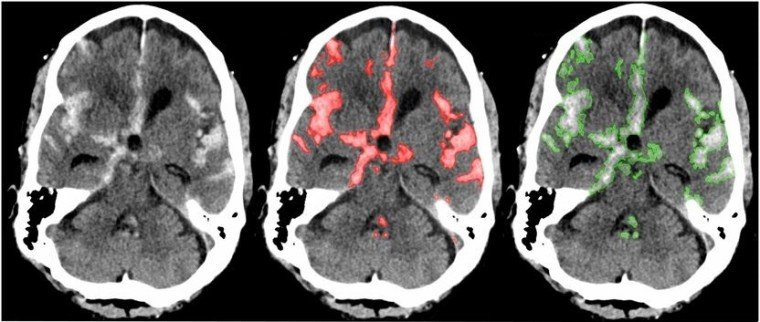

Trong những năm gần đây, công nghệ học sâu (deep learning) đã phát triển mạnh và có nhiều ứng dụng thực tiễn trong đời sống và cả y học. Nhóm nghiên cứu cho biết họ đã sử dụng kết hợp mạng neuron thần kinh một giai đoạn (single-stage), đầu cuối (end-to-end) và đầy đủ (fully) để đào tạo nên hệ thống chẩn đoán có độ chính xác tương đương với các bác sỹ X-quang có chuyên môn cao. PatchFCN có thể xác định và định vị được những bất thường trong bộ não mà nhiều bác sĩ X-quang vô tình bỏ qua.

Theo các chuyên gia, trong mô hình đào tạo, mỗi phim chụp CT được phân tích chỉ trong vòng vài giây. Sau đó, hệ thống sẽ đưa ra chẩn đoán về nguy cơ xuất huyết não, thông tin chi tiết và đo lường mỗi lần xuất huyết (nếu có).